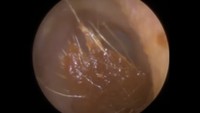

Hii, kotoran seperti ini tampaknya sudah melekat dan sulit diambil. (Foto: YouTube)